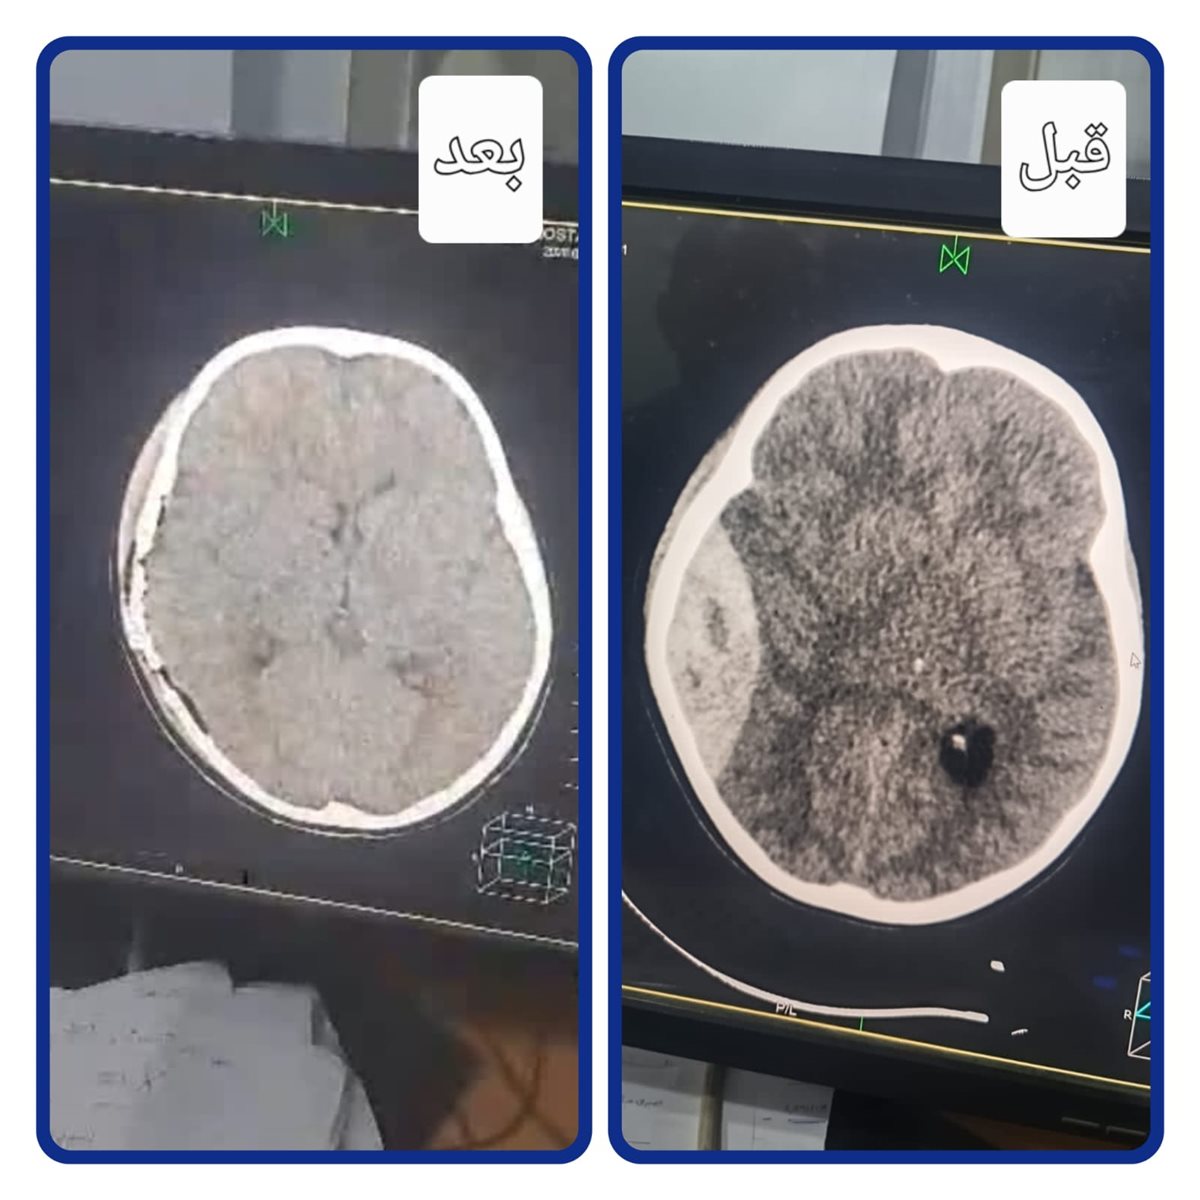

وكانت المستشفى قد استقبلت الحالة وهي تعاني من نزيف فوق الأم الجافية، مصحوبًا بتدهور شديد في درجة الوعي والإدراك، وعلى الفور تم التعامل مع الحالة بشكل عاجل، حيث جرى إدخال الطفل إلى غرفة العمليات وإجراء جراحة دقيقة لتفريغ النزيف بالمخ، مع حجزه بالعناية المركزة لمتابعة حالته الصحية.

وخلال المتابعة الدقيقة، أظهرت الأشعة المقطعية وجود تجمع دموي آخر، ما استدعى التدخل الجراحي العاجل للمرة الثانية خلال أقل من 24 ساعة، حيث تمكن الفريق الطبي من إجراء العملية بنجاح، مع تفريغ النزيف والسيطرة على مصدره، ما ساهم في تحسن الحالة بشكل ملحوظ، واستعادة المريض لدرجة وعي كاملة (15/15)، قبل أن يتماثل للشفاء ويغادر المستشفى بحالة جيدة.